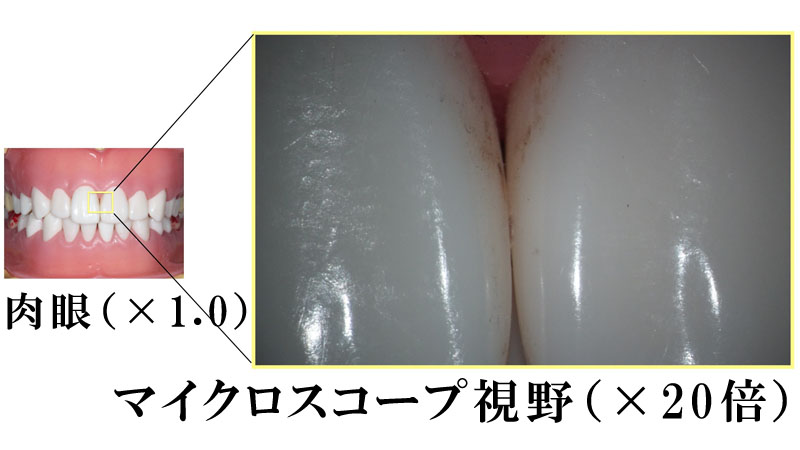

マイクロスコープを使用した診療イメージ

20倍の拡大視野で観察すると、虫歯や歯石などを細かく観察できます。